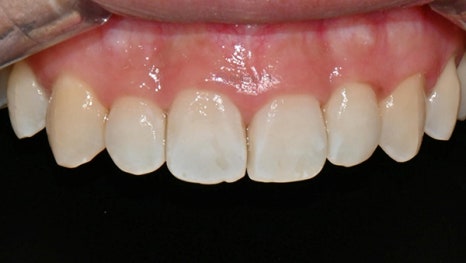

본 20대 여자 환자분은 약 한 달전 교정 치료를 끝마친 후에 앞니에 화이트 스팟이 생겼다는 이유로 감사하게도 경기도에서 저희 치과까지 찾아와주셨습니다. 일반적으로 교정 치료 후 생긴 반점치는 장치 형태 주변으로 생기는데, 본 환자의 경우 앞니 2개에 심하지는 않지만 중앙 부분에 화이트 스팟이 생겼습니다.

아이콘 치료 전후

아이콘 치료 직후 사진입니다. 아이콘 치료는 치아를 깎지 않기 때문에 마취 없이 간단하게 2030분 이내 치료가 가능하다는 장점이 있습니다. 아이콘 치료시 치아 전체를 건조시킨 상태로 유지를 해야 하기 때문에 치아가 일시적으로 chalky white하게 보이지만, 실제로 침이 있는 자연스러운 구강 내 상태로 보면 사진보다 훨씬 더 심미적으로 자연스럽게 보이며, 치료 12주 정도 지나면 훨씬 더 자연스러워보입니다. 치료 직후 처음으로 거울로 본인의 치아를 본 환자분의 첫마디도 "와우!" 였습니다 :)